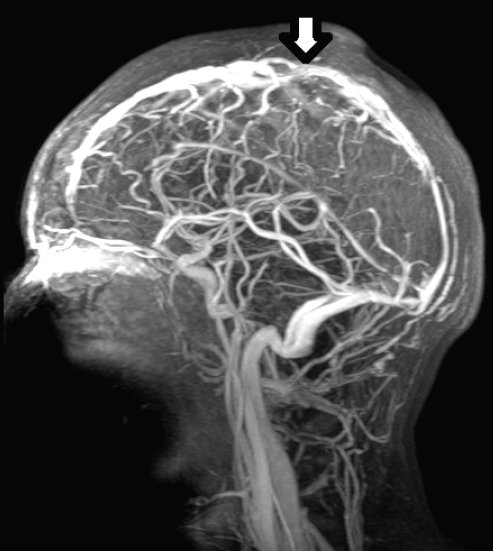

Good clinical response was noted during her follow-up visit. However, 3 weeks later she returned to our emergency department with fever, headache, and neck stiffness. A head CT scan revealed a right subdural empyema and partial thrombosis of the superior sagittal sinus. She was started on intravenous ceftriaxone, vancomycin, metronidazole, and heparin infusion. Magnetic resonance imaging and magnetic resonance venography scans characterized the extent of the cavernous sinus thrombosis (Figure 2).

Figure 2 — Magnetic resonance venogram of the head shows an occlusive filling defect in the superior sagittal sinus.